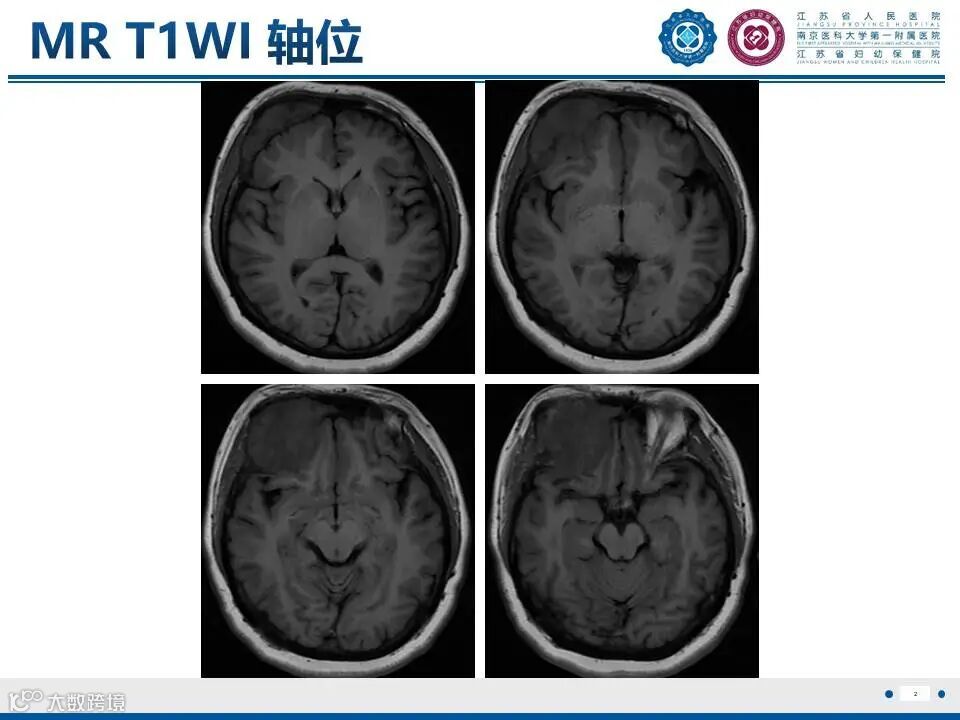

颅骨骨纤维异常增殖症——颅骨上的编织骨

颅骨骨纤维异常增殖症——颅骨上的编织骨 鼎湖影像